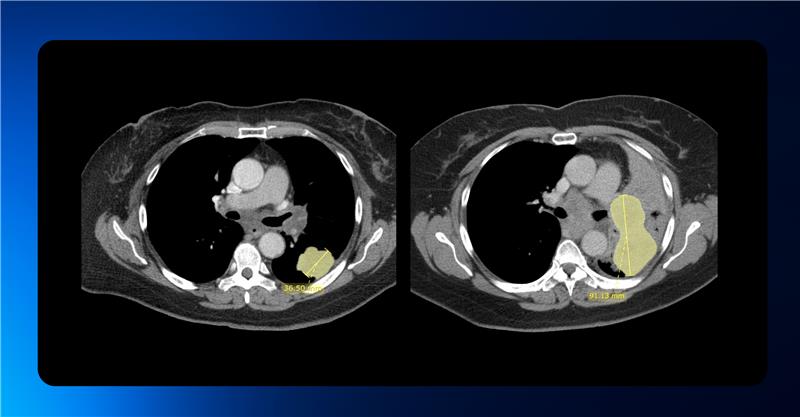

Streamlining RECIST Evaluation with AI

Designed to optimize radiology workflows, Quibim’s solution—integrated within the QP-Insights platform—leverages advanced deep learning algorithms to accelerate tumor response evaluation based on RECIST 1.1 criteria.

AI-driven tools are seamlessly embedded into the workflow to automatically detect, segment, measure, and track lesions in the lungs and liver. The algorithm is capable of identifying new lesions and monitoring existing ones across follow-up timepoints following the baseline scan.

Radiologists retain full control over the evaluation process, with the ability to manually adjust the AI-generated measurements and add lesions from other anatomical regions in an intuitive and user-friendly interface.

All data is automatically stored in a standardized digital format within the platform, enabling automated RECIST 1.1 response calculations and generating a final summary report of the complete assessment.